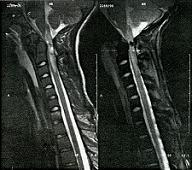

Στις περιπτώσεις αυτές χρειάζεται κατά κύριο λόγο μια αναλυτική, νευρολογική και ακτινολογική εξέταση (δες εικόνα) προκειμένου να αναλυθούν και να εκτιμηθούν ανάλογα όλα τα παθολογικά στοιχεία και οι δυσμενείς συνέπειες αυτού του είδους των τραυματισμών.

Πρόκειται για πολύ επικίνδυνους τραυματισμούς με σοβαρές συνέπειες όπως φαίνεται και στην εικόνα που μπορεί να είναι θλάσεις, συρίγγια κ.λ.π..